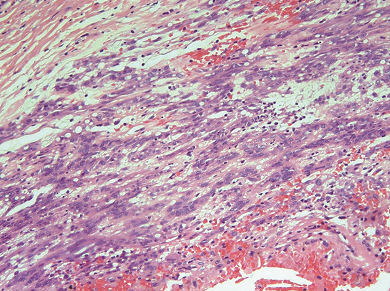

1小时条评论PDGFRA基因位于人类第4号染色体上,属于Ⅲ型酪氨酸激酶受体家族。D842V突变是PDGFRA基因编码活化环结构域的第18号外显子(Exon18)上的一种点突变,会导致PDGFRA结构异常,进而致使其下游信号通路的传导出现异常...